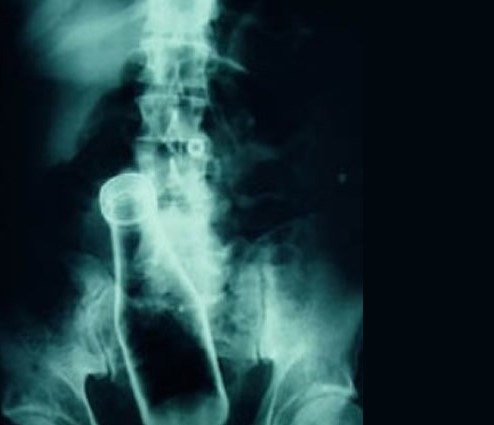

SE APRECIA AL EXAMEN RADIOGRAFICO PRESENCIA DE CUERPO EXTRAÑO (BOTELLA VIDRIO) EN REGION RECTAL Y COLON SIGMOIDES.